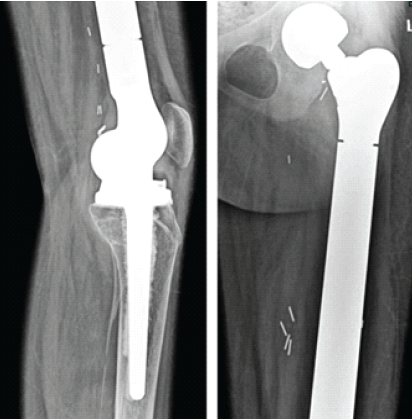

“Whoops Procedure” an Iatrogenic Indication for Total Femur Replacement in a Young Patient with Osteosarcoma. A Case Report

Varun Sanap , Sandesh Thete

………………………………p.95-100